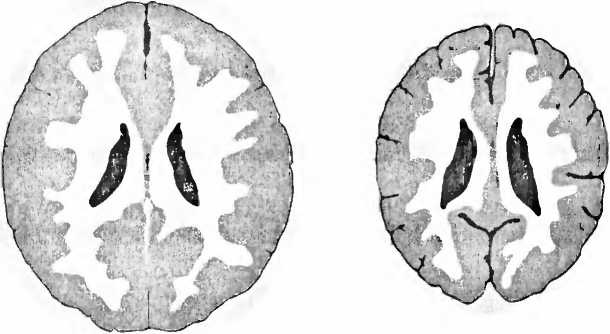

Рис. 6. Справа — томограмма мозга сильно запущенного трехлетнего ребенка, и для сравнения — томограмма мозга ребенка такого же возраста с нормальным развитием мозга (слева). У запущенного ребенка мозг значительно меньше, с увеличенными желудочками вентрикулами, полостями, черного цвета), по сравнению с мозгом нормально развивавшегося ребенка того же возраста. Кроме того между мозговыми извилинами видны увеличенные пространства из-за сморщивания (атрофии) коры больших полушарий (В. D. Perry, 2002).